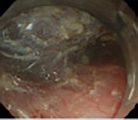

出血性胃十二指腸潰瘍や食道静脈瘤破裂などの上部消化管出血に対して、緊急内視鏡的止血術(ソフト凝固止血、クリッピング、EVLなど)にて治療を行い良好な成績を得ています。また、逆流性食道炎、胃十二指腸潰瘍、胃癌などの診断・治療を行っており、ルーチン検査には患者様の負担が少ない経鼻内視鏡も使用しています。胃十二指腸潰瘍の再発予防にはH.pylori除菌療法を外来にて施行しています。早期胃癌、胃腺腫など内視鏡的治療の適応となる腫瘍に対してはIT2ナイフなどを使用したESD(内視鏡的粘膜下層剥離術)・EMR/polypectomyによる内視鏡治療も施行しています。

図1-1

図1-2

図1-3

図1-4

図1:当院循環器内科でPCIを施行した後に軽度の貧血を認めたため、上部消化管内視鏡検査を施行したところ、胃前庭部大弯に8mm大の辺縁が不整な陥凹性病変を認め、早期胃癌0-IIc,分化型,深達度Mと診断しました。内視鏡的治療適応と診断し、ESD(内視鏡的粘膜下層剥離術)を施行しました。特に合併症なく終了し、術後病理標本では、Adenocarcinoma(tub1), M, cut end(-)であり治癒切除の判定でした。